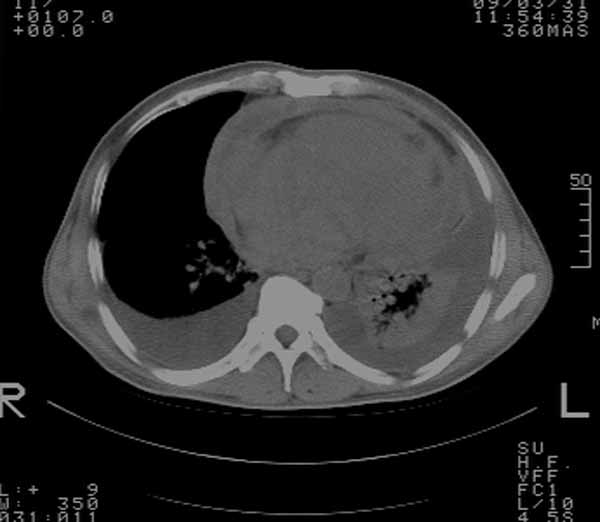

以下是引用余辉在2009-3-31 18:43:00的发言:[br]肺水肿,双侧心腔积液,心包积液,心影增大,疑似心衰

以下是引用wangyong1977在2009-3-31 20:46:00的发言:[br]肺水肿,双侧胸腔积液,心包积液,心影增大,疑似心衰 [br]

以下是引用宇宙ct在2009-3-31 18:57:00的发言:[br]肺水肿,双侧心腔积液,心包积液,心影增大,疑似心衰 [br] [br]